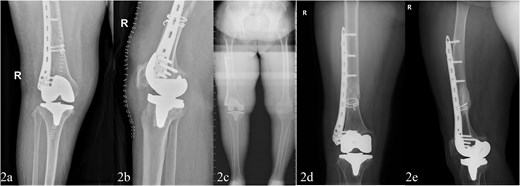

The procedure was performed under spinal anesthesia with cefazolin and tranexamic acid administered for infection prophylaxis and bleeding control. A midline anterior knee incision was made to expose the joint and fracture site. Intraoperatively, a spiral fracture and full-thickness cartilage wear were found. The surgical steps included: (i) provisional fracture reduction with cerclage wires; (ii) performing necessary tibial, femoral, and patellar cuts and trial reductions (Femoral alignment was achieved using an intramedullary rod inserted after provisional fracture stabilization with bone clamps and cerclage wires); (iii) TKA using a standard cruciate-sacrificing prosthesis; (iv) application of a locked compression plate for fracture fixation; (v) wound closure after stability testing. The TKA prosthesis used was the Attune primary TKA system (DePuy Synthes). The procedure lasted 124 min with an estimated blood loss of 105 ml. Immediate post-operative imaging is shown in Fig. 2a and b.

Post-operative fracture fixation with TKA and locking plate (a and b). Four years later, healed for review only fracture with implants in situ (c–e).

The patient resumed light housework at 8 weeks and walked independently without aids at 12 weeks. At the final follow-up, 4 years post-surgery, the patient demonstrated substantial improvement. The Oxford Knee Score increased to 36.8, the VAS pain score decreased to 1.9, and radiographs showed no implant loosening and normal knee alignment (Fig. 2c–e). The patient regained independent ambulation and had an improved quality of life.